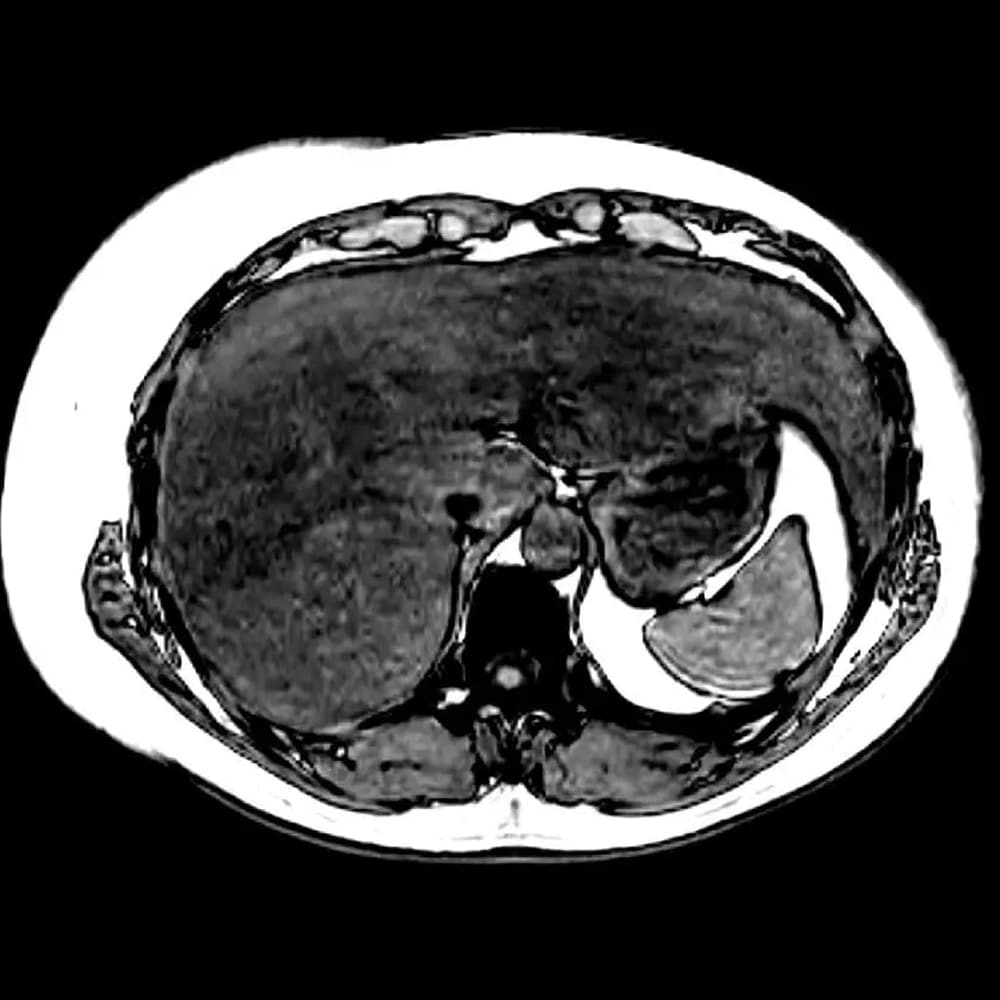

Liver Fat Quantification MRI

Our Liver Fat Quantification MRI is a non-invasive scan that measures how much fat is stored in your liver. This study helps assess hepatic steatosis (fatty liver), which can be related to conditions such as non-alcoholic fatty liver disease and other liver or metabolic issues. The scan takes about 30 minutes and does not require contrast. This is a private, self-pay service and is not covered by OHIP.

Measures the degree of fat inside liver cells or hepatic steatosis / fatty liver

Uses magnetic fields to image the liver

Images are interpreted by a radiologist with a fat-quantification score